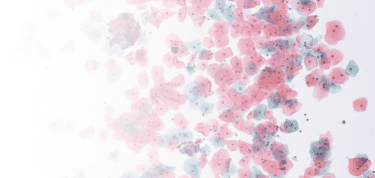

For new technicians, medical students, and experienced pathologists in need of ongoing training, Techcyte provides a simple web-based platform to learn, review, and get tested on blood, fecal, pap smears, fecal O&P, and other custom-defined sample types.

The Fusion Education Suite draws on a diverse set of images for each atlas.

Schools, labs and hospitals can select a pre-existing set of images or create their own atlases for learning, reviewing and testing purposes.

Once the images are selected and classifications are confirmed, students are presented with training images and eventually test their skills by classifying images selected at random.